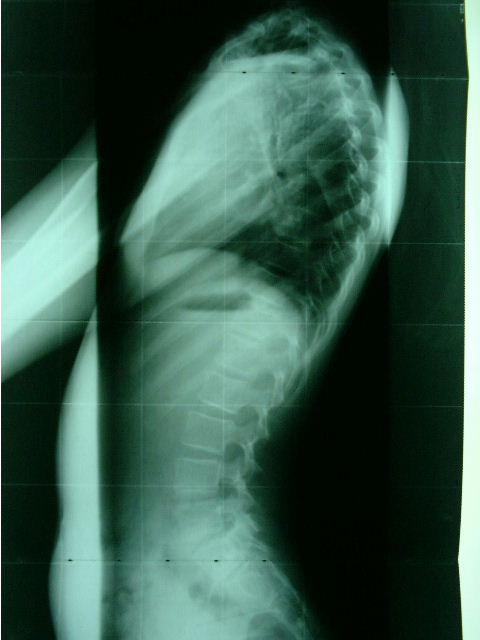

Armando Vinci grazie per la tua accurata risposta.Ti invio le mie radiografie.

Anteprime Allegate Anteprime Allegate Clicca l'immagine per ingrandirla.

ID: 2142   Clicca l'immagine per ingrandirla.

Nome: senza titolo1.jpg‎

Visualizzazioni: 1049

Dimensione: 14.5 KB

ID: 2143

***Premessa, ciò che ti dirò è una valutazione fatta solo vedendo 2 radiografie, nemmeno di alta qualità***

La ipercifosi è causata da una iperlordosi, chiaramente visibile nella prima radiografia.

Nella seconda si vede bene l'asimmetria del bacino, che determina scoliosi da compensazione.